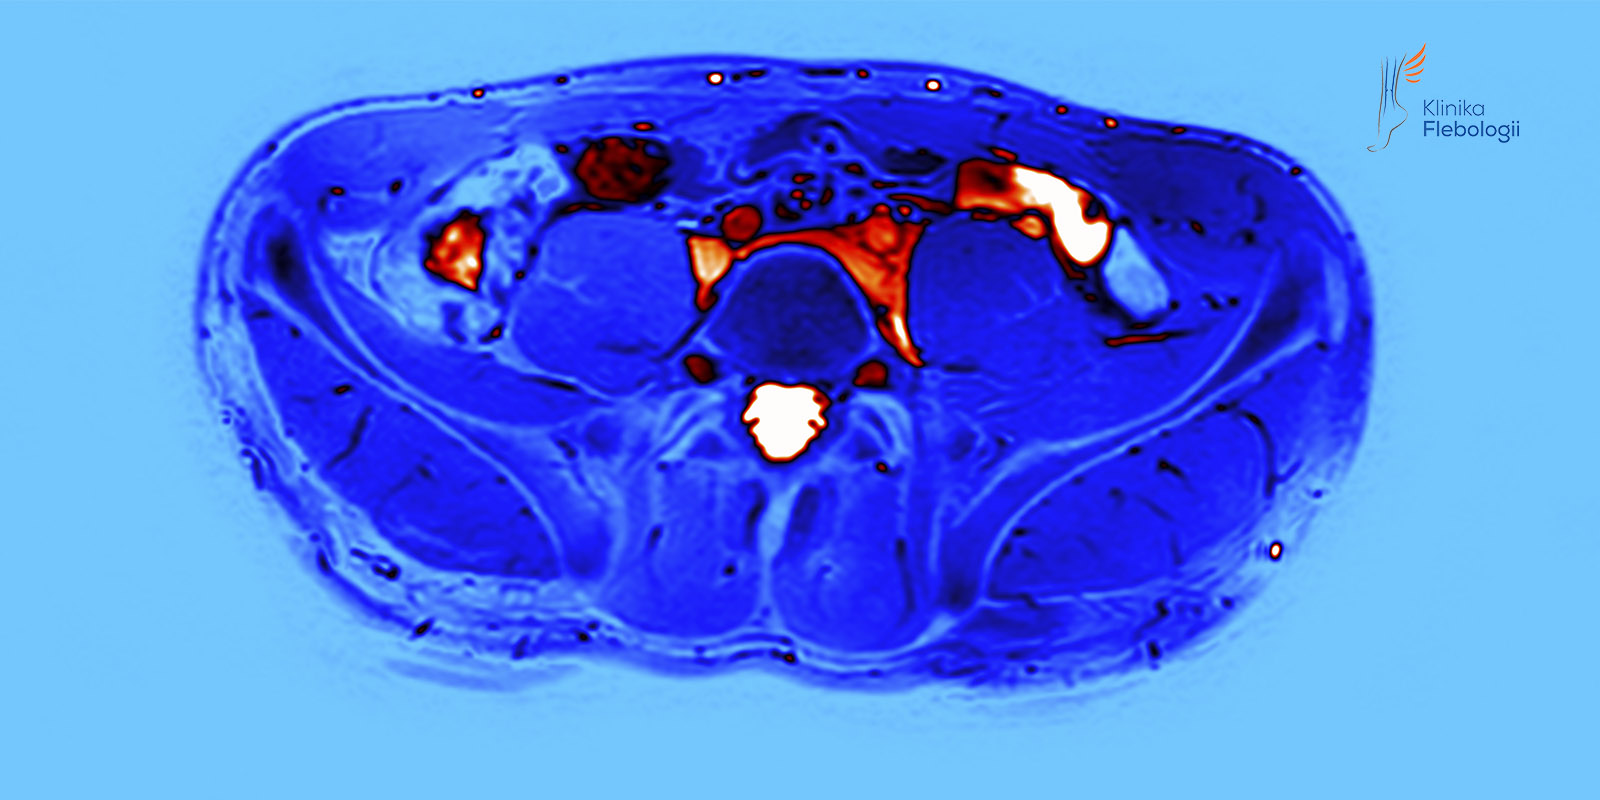

Współczesne badania obrazowe, w tym wykorzystywane na co dzień w Klinice Flebologii badania USG Doppler żył miednicy i jamy brzusznej oraz wenografia rezonansu magnetycznego (MRV), sugerują, że również u panów znaczna część przypadków niewydolności żylnej kończyn dolnych ma charakter wtórny.

Przyczyną wtórnej niewydolności żylnej kończyn dolnych u mężczyzn są anatomiczne nieprawidłowości układu naczyń żylnych. Podobnie, jak u kobiet, może występować ucisk na lewy spływ biodrowy oraz zjawisko „dziadka do orzechów” z niewydolnością lewej żyły gonadalnej (zwanej inaczej żyłą jądrową), prowadząca do powstania żylaków powrózka nasiennego.

Okazuje się, że większość mężczyzn, u których w młodym wieku pojawiają się poszerzone drobne naczynia, tzw. teleangiektazje żylne, a później żylaki o rozkładzie atypowym, ma niewydolność żylną miednicy. Najczęściej jest ona spowodowana dysfunkcją żył gonadalnych, tj. niewydolnością lewej żyły jądrowej, rzadziej ich niewydolnością obustronną.

Z praktyki zespołu Kliniki Flebologii wynika, iż duże żylaki (śr. > 5 mm) zlokalizowane w worku mosznowym często wynikają z przyczyn, które w rutynowej diagnostyce urologicznej są zwykle pomijane. Z tego względu w diagnostyce rozszerzonej zalecane jest wykonanie badań USG Doppler żył miednicy i jamy brzusznej oraz wenografii metodą rezonansu magnetycznego.